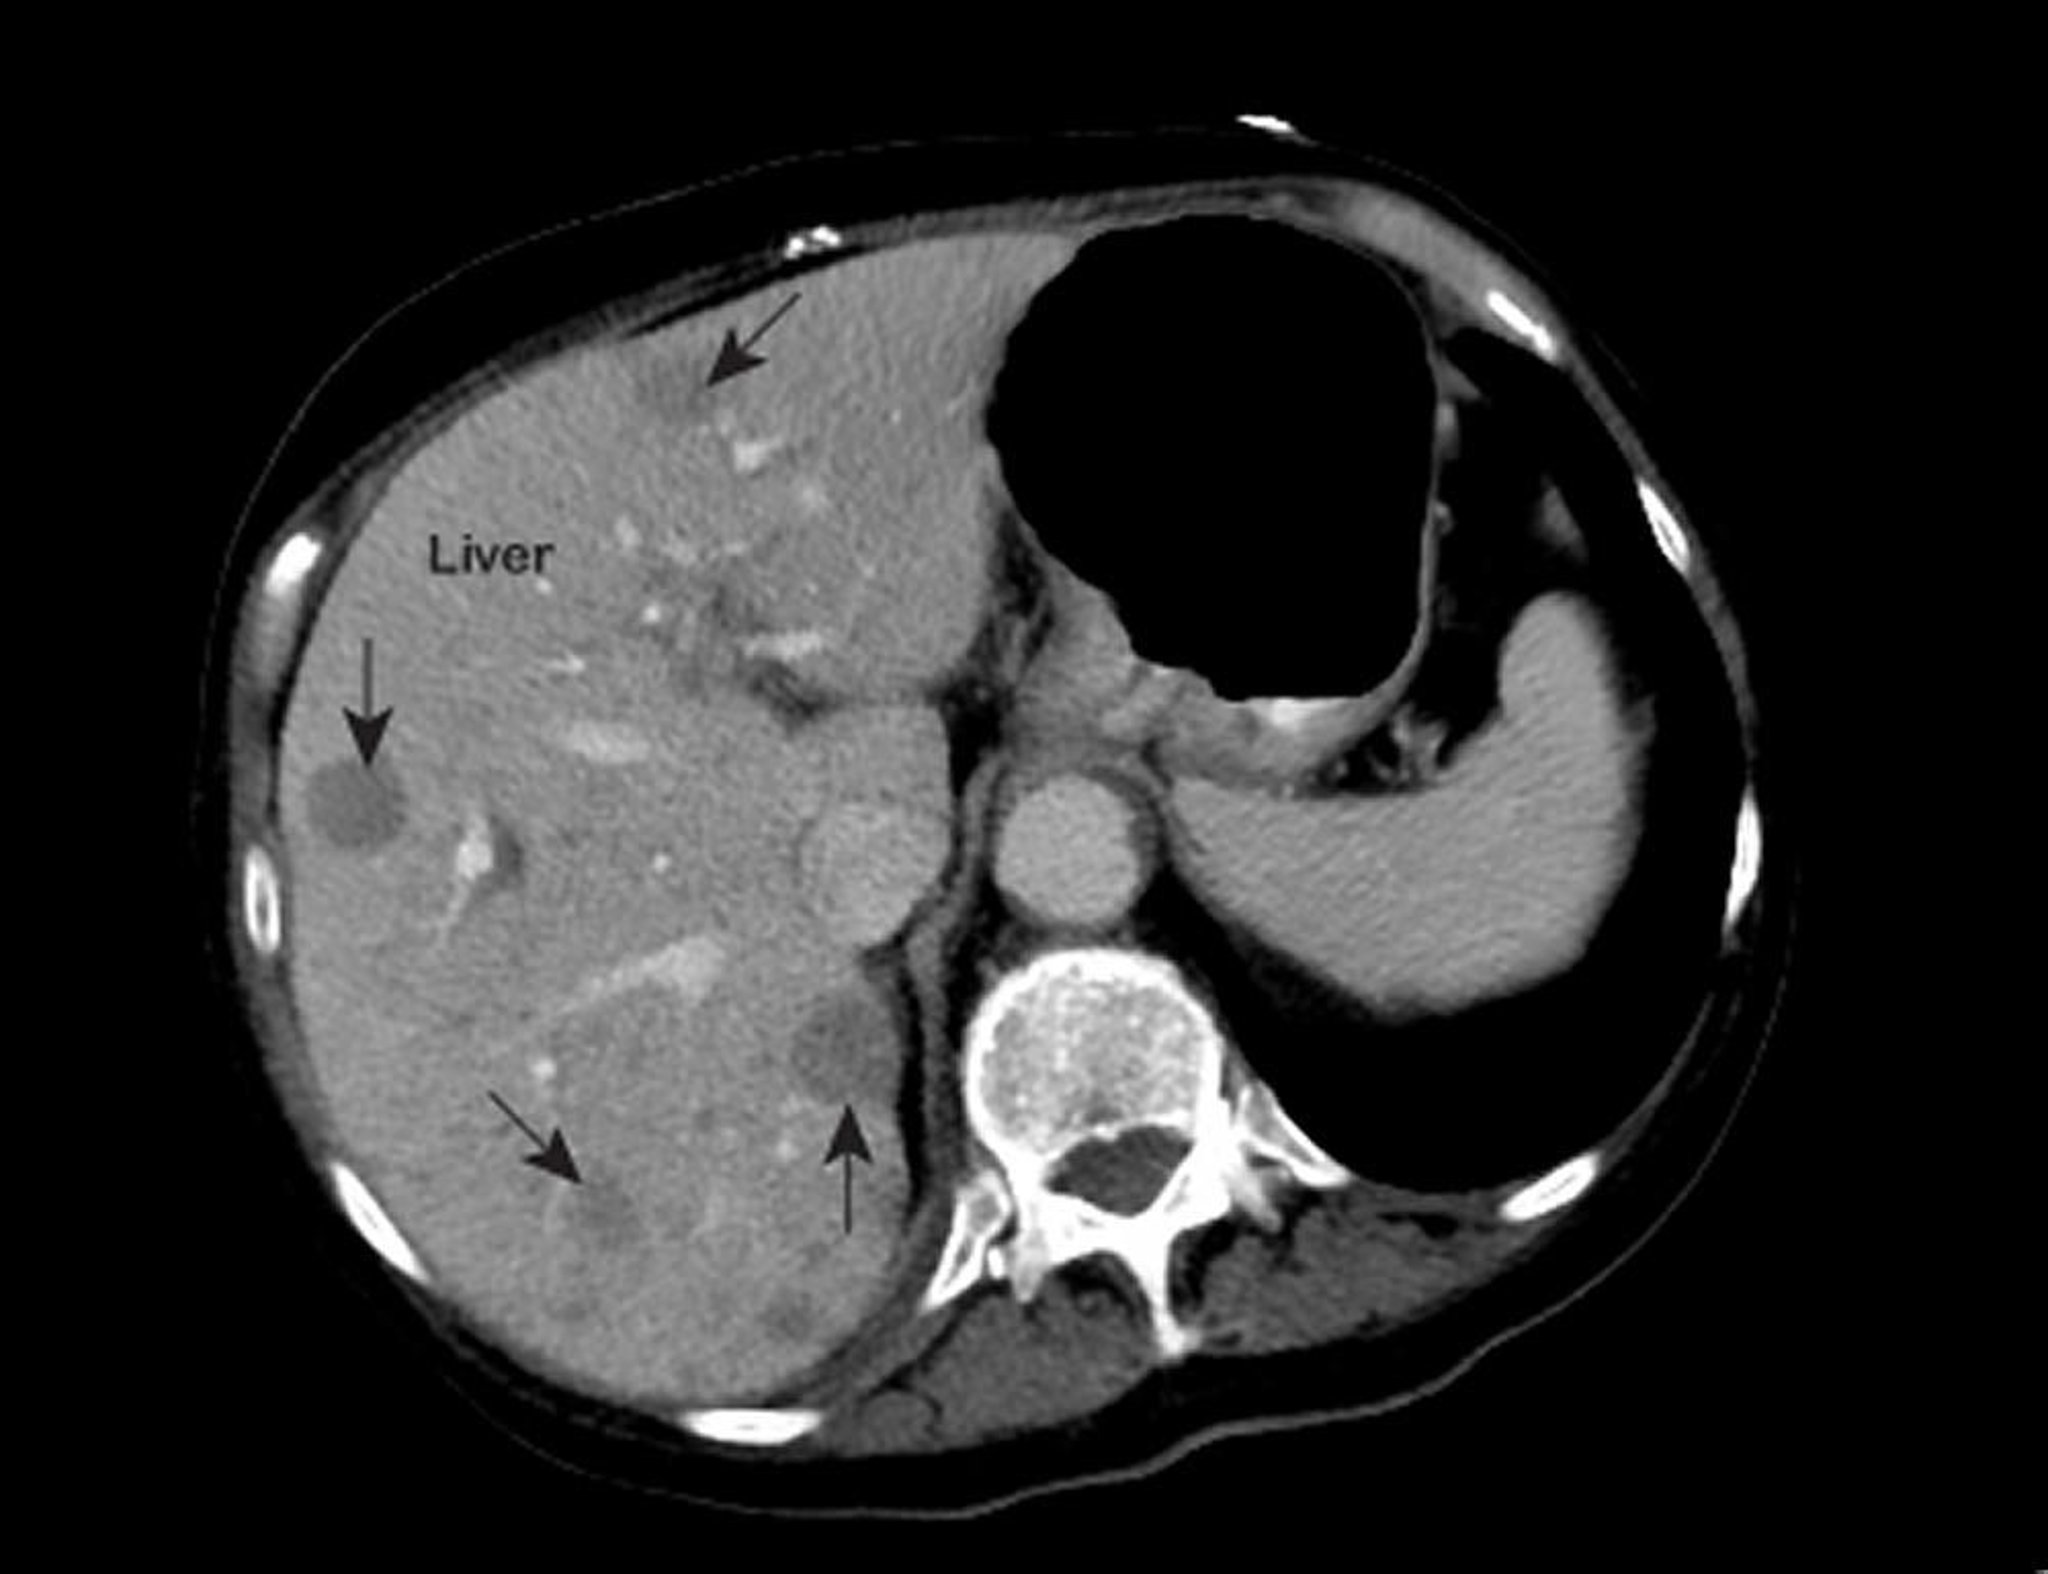

Cancer métastatique du foie

Une IRM thoracique anormale montre des zones de faible atténuation (marquées par des flèches) à l'intérieur du foie. Cet aspect est typique du cancer du foie métastatique.

Photo courtesy of Patrick O’Kane, MD.